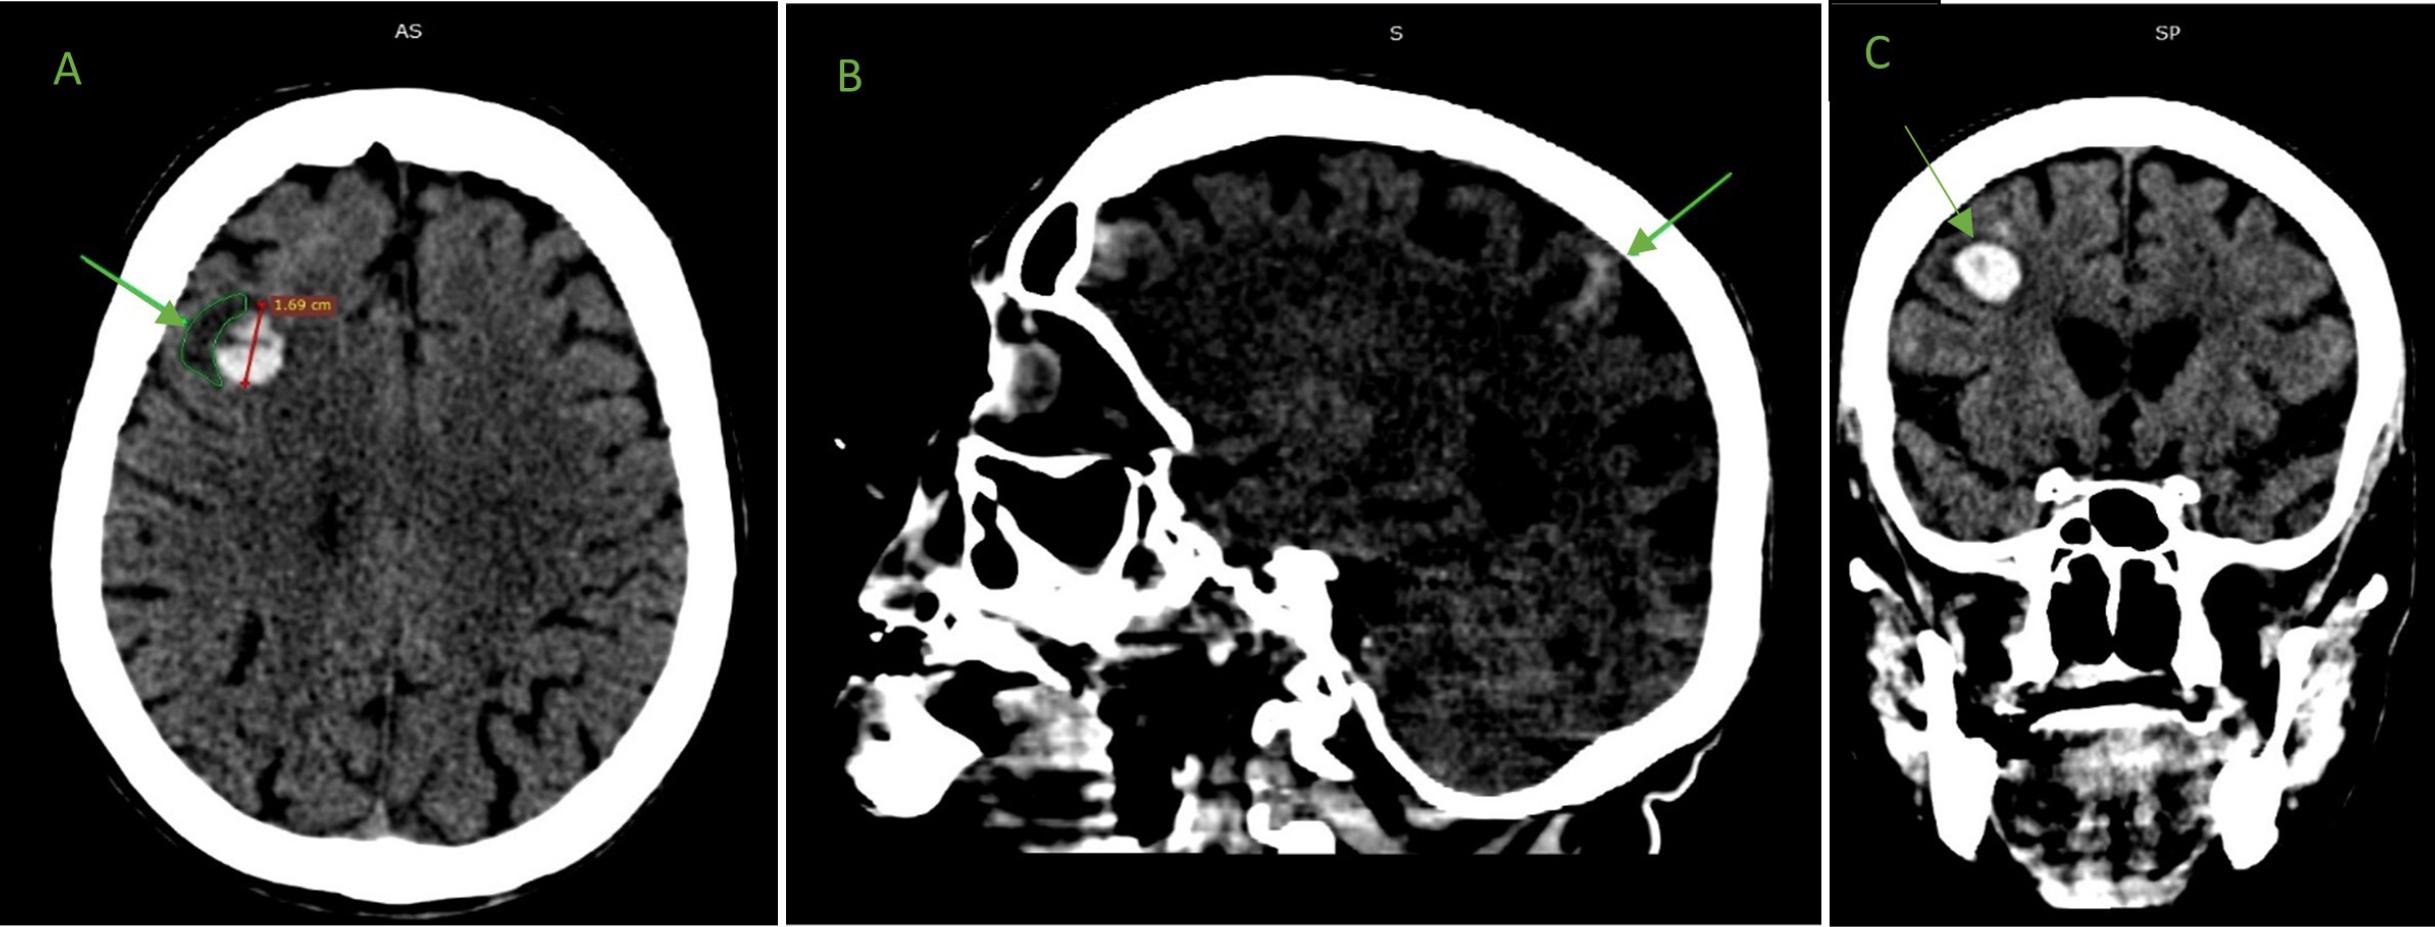

Computed tomography of the brain showing (A) frontal intraparenchymal cerebral hemorrhage and perilesional edema in transversal view; (B) subarachnoid hemorrhage in sagittal view; and (C) frontal intraparenchymal hemorrhage in frontal view.

The arrows indicate (A) a 17 mm frontal hematoma with peri-hemorrhagic edema; (B) left parietal subarachnoid hemorrhage; and (C) frontal hematoma.